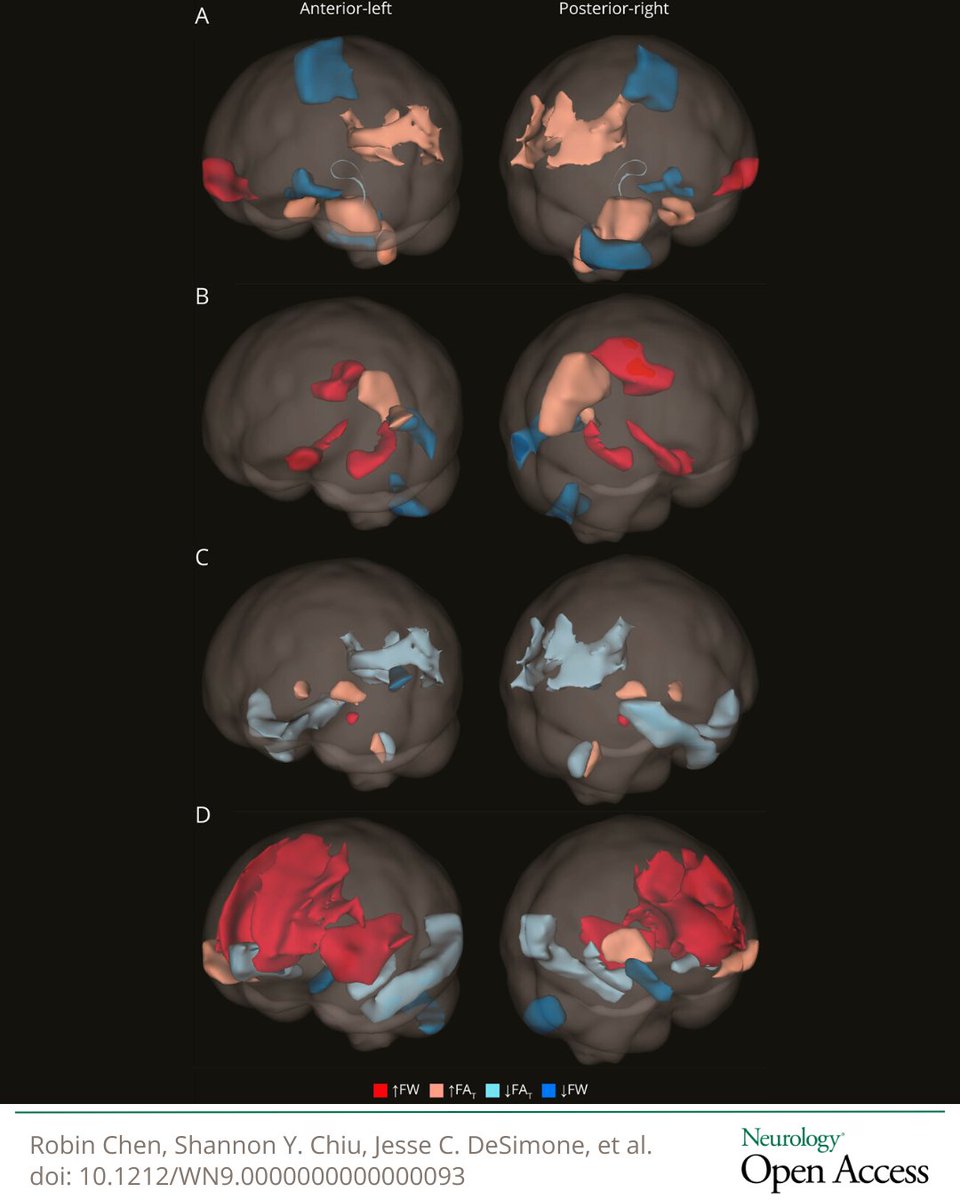

The findings from this study found that carrying the minor allele at an AQP4 haplotype was associated with better verbal episodic memory, larger hippocampal volumes, lower amounts of brain free water, and lower #dementia risk: hubs.la/Q04cgmv90 #NeuroTwitter

GreenJournal's tweet image. The findings from this study found that carrying the minor allele at an AQP4 haplotype was associated with better verbal episodic memory, larger hippocampal volumes, lower amounts of brain free water, and lower #dementia risk: hubs.la/Q04cgmv90